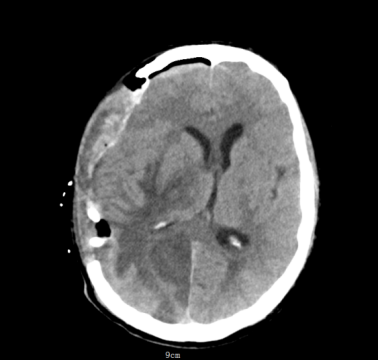

凌晨5点,神经医学科突然响起急促的电话铃声。“有一名48岁男性患者突发昏迷!双侧瞳孔已散大到5mm,对光反射消失,CT提示右侧颞顶枕叶巨大占位性质待查,中线结构明显移位,考虑脑脓肿或脑肿瘤合并脑疝!”电话那头,急诊医生语气急促。

影像医学科王樱花主任阅片后,考虑脑脓肿合并急性脑疝。脑疝是颅内压增高最危险的并发症之一,堪称大脑“断电”前兆。当颅腔内某一部分压力骤增,脑组织被挤压到另一个腔室,压迫脑干,可迅速导致呼吸心跳停止。而脑脓肿是一种由细菌、真菌或寄生虫引起的颅内化脓性感染,若不及时处理,脓肿增大压迫脑干,后果不堪设想。

该患者MR显示:右侧顶枕叶类圆形低密度影,周围水肿明显,中线结构左移超过1cm脑室受压变窄,环池显示不清,提示小脑幕切迹疝早期,已处于濒死边缘。

凌晨六点,患者被推进手术室,一场与死神的赛跑就此展开。麻醉科周愚主任亲自上阵,确保术中生命体征平稳。神经医学科团队实施急诊标准大骨瓣开颅术。在显微镜下精准穿刺,抽出黄色脓液约30ml,颅压瞬间下降,显微镜下脓肿完整切除。经过手术团队6小时的全力救治,患者术后瞳孔回缩,对光反射逐渐恢复。术后患者被转入ICU监护,继续抗感染、控制颅压、营养支持等综合治疗。